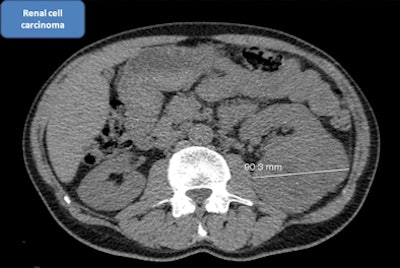

![]() |

| An axial view from a low-dose CT lung screening exam reveals the presence of a large renal tumor. Image courtesy of Dr. Zaigham Saghir. |